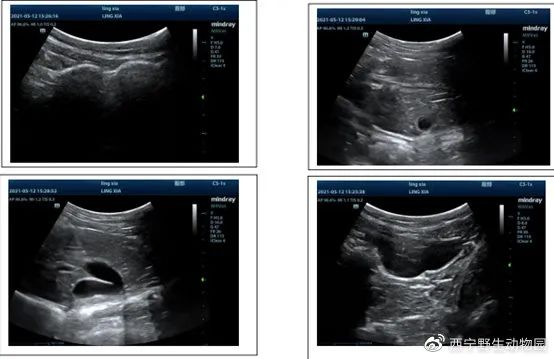

凌夏B超结果

X光检查

5月12日上午,中国农业大学动物医学院副院长金艺鹏教授团队抵达西宁野生动物园,与救护中心工作人员共同对雪豹进行麻醉体检。体检结果显示,该雪豹为雌性亚成体,准确年龄应为1岁,体长82cm,体重27kg。根据其膘情显示,该小野豹在救助前的野外生活状况应当非常不错。此外,检查发现该雪豹存在细菌感染,但救助人员表示,细菌感染可能与其被救助前长时间淋雨有关。